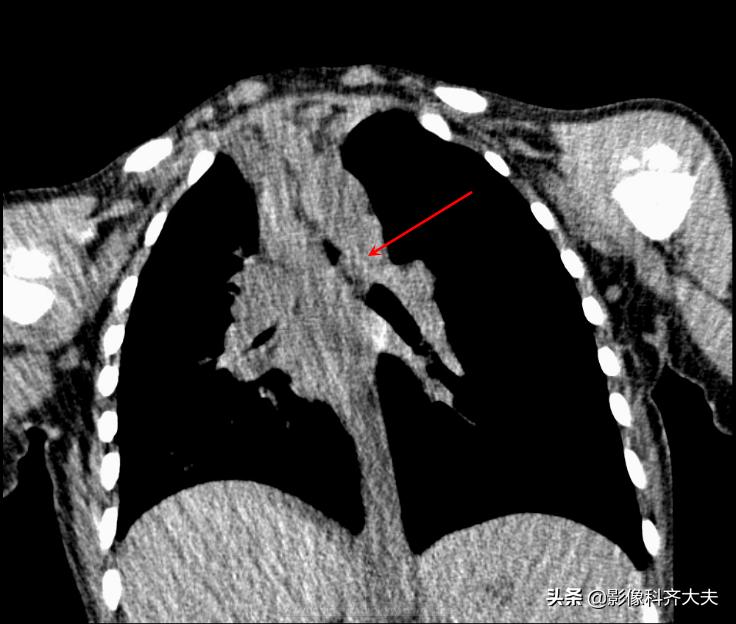

病例5、病史:女,1岁,咳喘12天无好转

轴位图

轴位显示左肺明显肺气肿,左侧支气管似有异常。为进一步明确诊断,遂进行CT三维重建

进行MPR(多平面重组)冠状位重建,清晰显示左侧左侧支气管有异物。

最小密度投影重建对于异物的显示更加清晰,红色箭头所示。

病例6、病史:女,两岁,吃花生时喝水引起呛咳。

轴位显示左侧支气管疑似异物,红色箭头。

冠状位重建清晰显示左侧支气管异物,红色箭头所示。

最小密度投影显示的更加清楚。

这是CPR(曲面重建),即单独对左侧支气管进行重建显影,清晰显示异物。

曲面重建后在进行最小密度投影重建,异物显示的更加清晰。

病例7、病史:患儿,女,16个月,吃饭呛咳,来院就诊。(图片来源:邯郸市第一医院)

图中CT轴位扫描及MPR冠状位重建,清晰显示左左侧支气管异物,红色箭头所示。

MinIP(最小密度投影重建)可准确直观显示异物的形态、大小、位置、堵塞程度等各种相关情况。可有效弥补X线胸片和常规CT诊断上的不足,作为支气管镜前筛查和手术定位的重要依据。

MinIP(最小密度投影)对气管、支气管等低密度组织的组织结构较为敏感,可清晰显示气管、支气管的解剖结构,异物情况,气管支气管形态,病变情况等等,效果显著优于X线平片和轴位CT,可为支气管镜取异物提供重要参考。